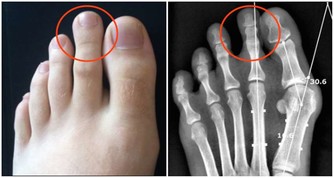

腳因為與心臟距離最遠,因此,血從心臟流到腳尖的過程也較長,很容易出現末梢迴圈障礙,導至供血不足;一些新陳代謝的廢物和各種毒素可能在足部積存下來,產生某種毒素,引起關節炎和一些器官的病變。 古人經常泡腳,用手按摩自己的腳心,天天散步,就是把氣血引到腳上去,只要新鮮的血液能引到腳上,令到氣血暢通,便可帶走在足部積存的代謝後廢物,運到腎臟處理後排出體外。 下肢血液回流心臟時,除胸腔吸氣運動產生的胸腔負壓和心臟舒張期產生的負壓吸引等作用外,主要依靠下肢肌肉在運動時的肌肉擠壓作用,特別是小腿肌肉(腓腸肌和比目魚肌是主要的「肌肉泵」)的擠壓作用,並藉助於靜脈瓣膜的單向開放功能,使靜脈血由遠端向近端、由淺靜脈向深靜脈流動,最後回流到心臟;我們把小腿肌肉的擠壓作用稱作「肌肉泵」作用,亦被稱為「第二心臟」。 下肢血液迴圈功能不佳,可影響人體各個器管的生理功能,導致各種疾病的發生,由此可以看出離心臟最遠的腳部肌肉的重要性。 雙腳的血液迴圈順暢,將促使全身的血液大循環亦處於良好狀態,你就可以延緩衰老。